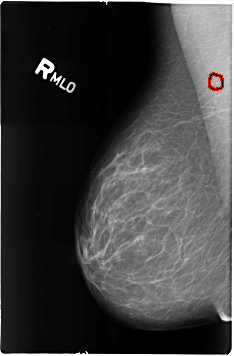

B_3165_1.RIGHT_MLO

RIGHT_MLO LINES 4624 PIXELS_PER_LINE 3032 BITS_PER_PIXEL 12 RESOLUTION 50 OVERLAY

FILE: B_3165_1.RIGHT_MLO.OVERLAY

TOTAL_ABNORMALITIES 1

ABNORMALITY 1

LESION_TYPE CALCIFICATION TYPE LUCENT_CENTERED DISTRIBUTION N/A

ASSESSMENT 2

SUBTLETY 3

PATHOLOGY BENIGN

TOTAL_OUTLINES 1

BOUNDARY